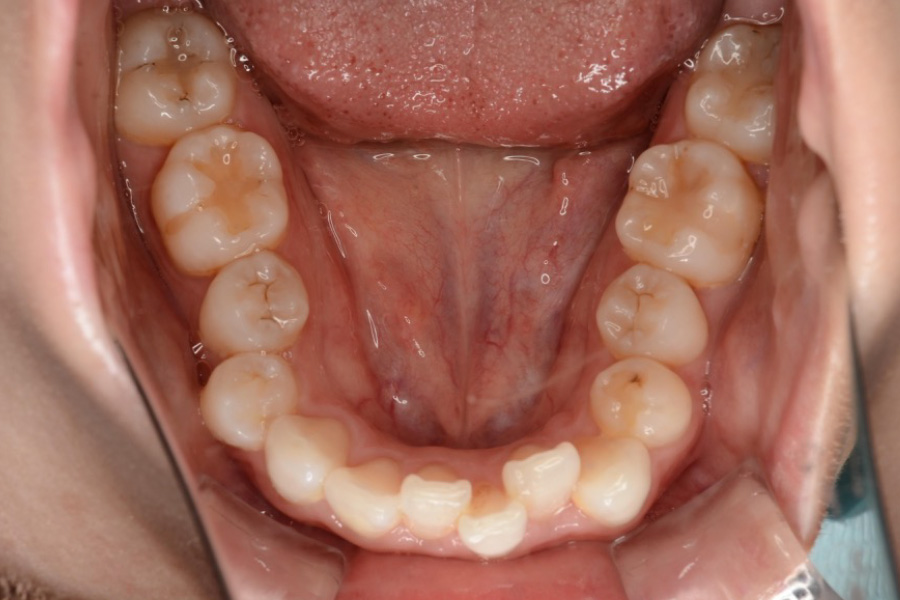

治療後

主訴 下の歯のガタつき、前歯の突出感が気になる

期間 2年半

治療内容 インビザライン矯正

非抜歯